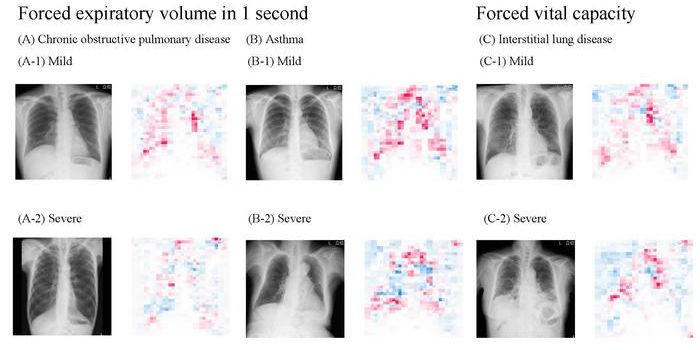

JUL 12, 2024TechnologyHow can artificial intelligence (AI) contribute to the healthcare industry? This is what a recent study published in The ...